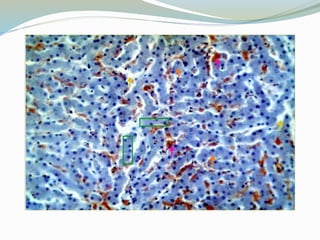

Células enteroendócrinas

 Se encuentran en las criptas y vellosidades

 Secretan péptidos reguladores activos que participan

en la secreción gástrica, la motilidad intestinal, la

secreción pancreática y la contracción de la vesícula

biliar